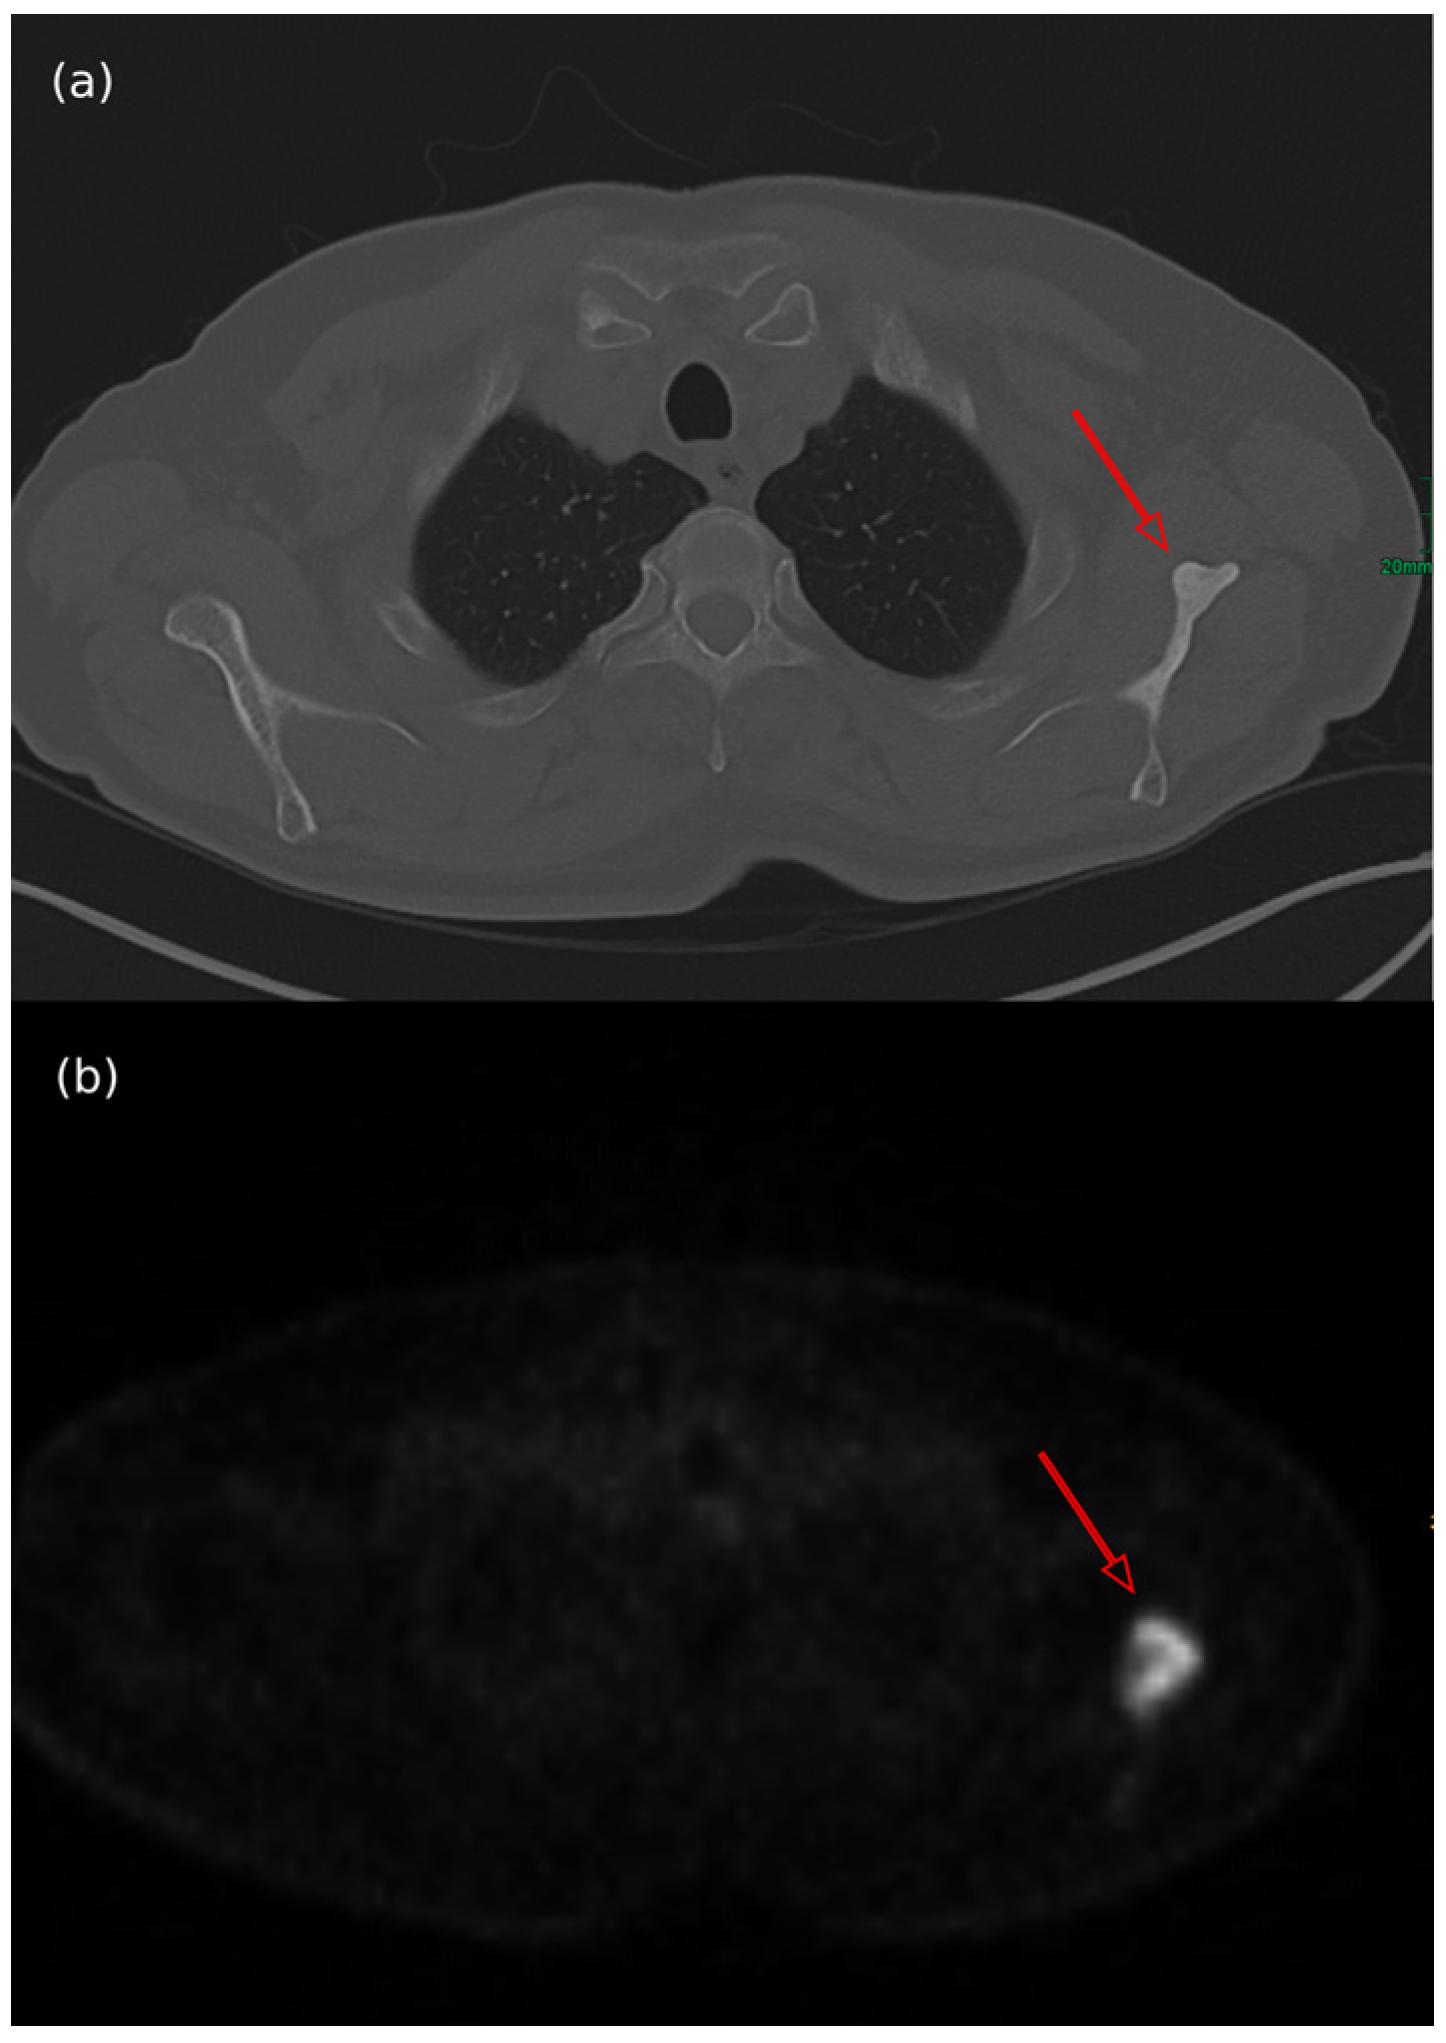

- Oh, H.Y.; Kim, D.; Choi, Y.S.; Kim, E.K.; Kim, T.E. Merkel Cell Carcinoma of the Trunk: Two Case Reports and Imaging Review. J. Korean Soc. Radiol. 2023, 84, 1134–1139. [Google Scholar] [CrossRef]